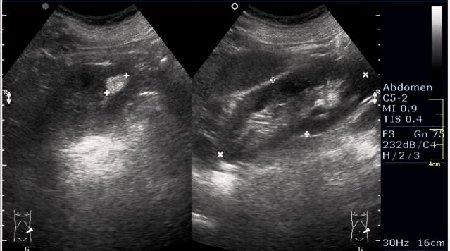

PS. Кстати, а что это у нее рядом с правым надпочечником?

Область правого надпочечника

PS. А надпочечник в срез не попал. Что-то, возможно, прилежит к области проекции надпочечника и к верхнему полюсу почки.